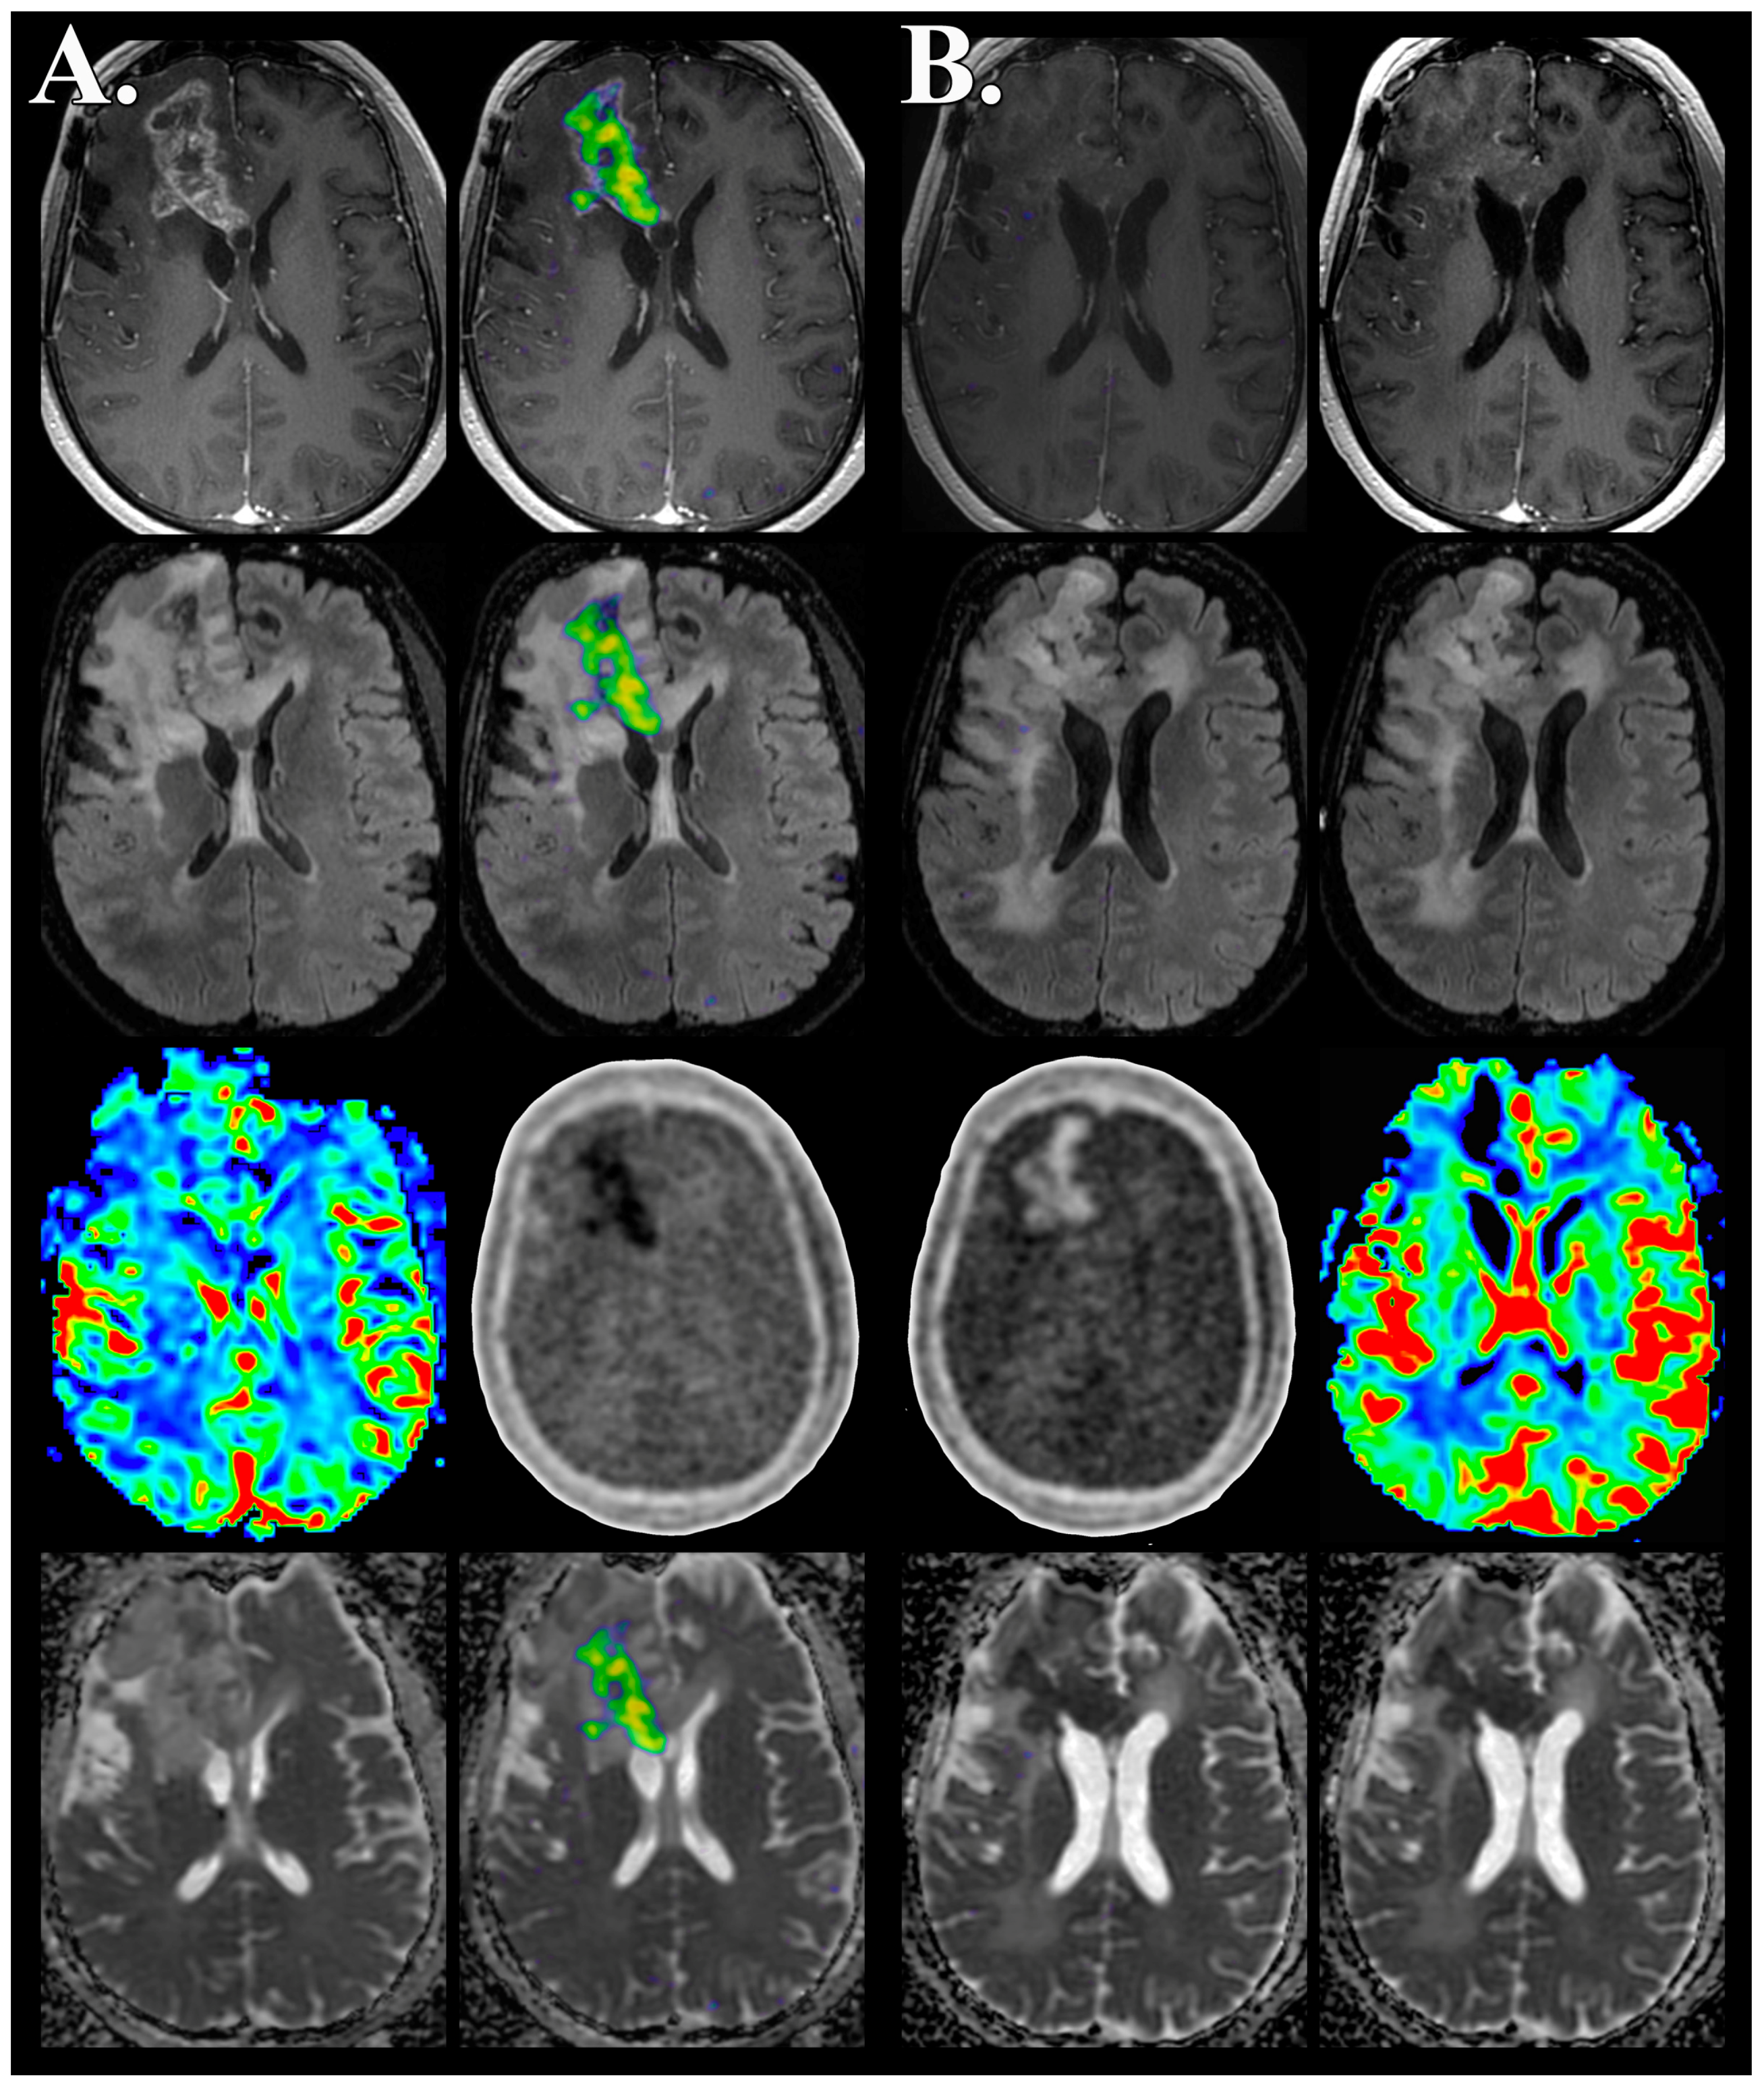

- Barajas, R.F., Jr.; Pampaloni, M.H.; Clarke, J.L.; Seo, Y.; Savic, D.; Hawkins, R.A.; Behr, S.C.; Chang, S.M.; Berger, M.; Dillon, W.P.; et al. Assessing Biological Response to Bevacizumab Using 18F-Fluoromisonidazole PET/MR Imaging in a Patient with Recurrent Anaplastic Astrocytoma. Case Rep. Radiol. 2015, 2015, 731361. [Google Scholar] [CrossRef] [PubMed]

- Barajas, R.F., Jr.; Butowski, N.A.; Phillips, J.J.; Aghi, M.K.; Berger, M.S.; Chang, S.M.; Cha, S. The Development of Reduced Diffusion Following Bevacizumab Therapy Identifies Regions of Recurrent Disease in Patients with High-grade Glioma. Acad. Radiol. 2016. [Google Scholar] [CrossRef] [PubMed]

- Barajas, R.F., Jr.; Phillips, J.J.; Parvataneni, R.; Molinaro, A.; Essock-Burns, E.; Bourne, G.; Parsa, A.T.; Aghi, M.K.; McDermott, M.W.; Berger, M.S.; et al. Regional variation in histopathologic features of tumor specimens from treatment-naive glioblastoma correlates with anatomic and physiologic MR Imaging. Neuro Oncol. 2012, 14, 942–954. [Google Scholar] [CrossRef] [PubMed]

- Barajas, R.F., Jr.; Hodgson, J.G.; Chang, J.S.; Vandenberg, S.R.; Yeh, R.F.; Parsa, A.T.; McDermott, M.W.; Berger, M.S.; Dillon, W.P.; Cha, S. Glioblastoma multiforme regional genetic and cellular expression patterns: Influence on anatomic and physiologic MR imaging. Radiology 2010, 254, 564–576. [Google Scholar] [CrossRef] [PubMed]